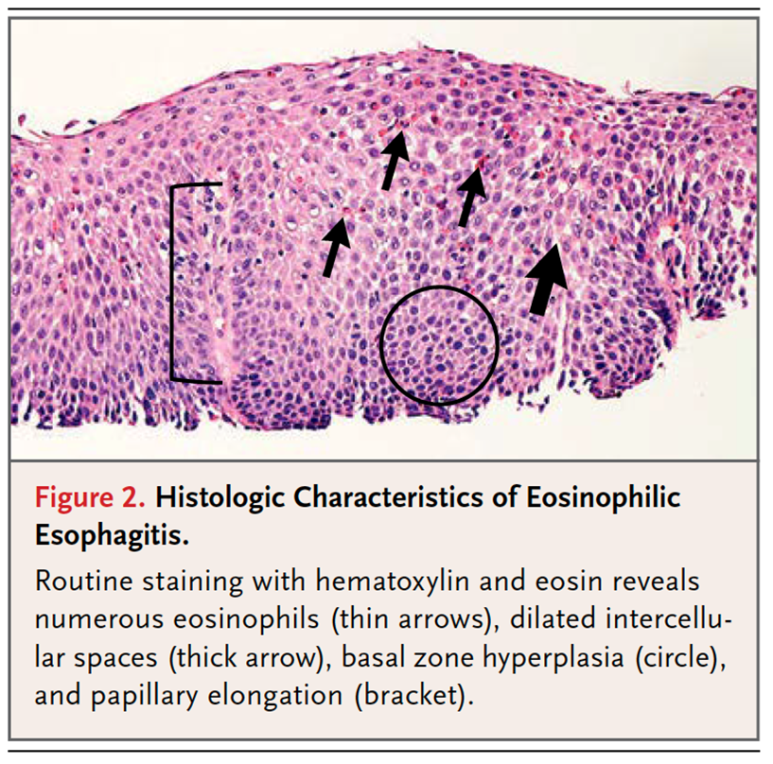

조직검사소견은 호산구가 H PF당 15개 이상 검출되는 것이 가장 중요하며, ECM 공간이 더욱 증가하고 basal zone hyperplasia가 동반되는 특징을 가지고 있습니다.

조직검사는 유럽의 경우 6개소를 시행할 것을 권고하고, 미국의 경우 2-4개의 promixal, distalesophagus에서 시행할 것을 권고하고 있습니다.진단 기준 상의 내용을 종합하여 호산구 식도염의 진단 기준을 확인하게 됩니다.먼저 전 세계에서 모여 만든 AGREE 컨퍼런스에서는 식도의 Dysfunction이 발생하는데 아토피 소인이 있고 내시경적으로 특징적인 소견이 있으며 조직학적으로 HPF당 15개의 호산구가 확인되어야 합니다. 이때 중요한 것은 호산구의 침착이 식도에만 국한되어야 하며 다른 2차적인 원인에 의해 식도 내 호산구가 증가하지 않는 것입니다. 즉, 다른 질환 없이 식도로만 호산구가 증가한다는 것을 의미합니다.